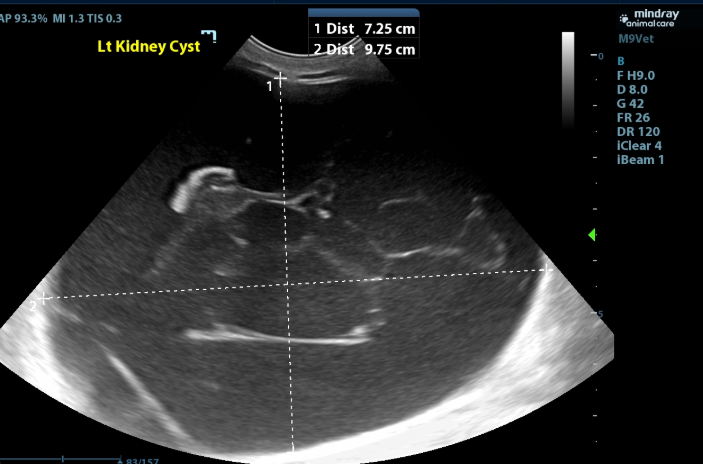

Kidneys and Ureters:

- There is a severely enlarged cystic structure (at least 7.3x9.8cm) surrounding the left kidney that is filled with mildly echogenic fluid with thin, hyperechoic strands extending through the cavitary region creating a septate appearance. Some of these strands connect to a 2.0x0.6cm hyperechoic heterogenous collection of tissue that sits along the capsule of the left kidney.

Cystic Structure around Left Kidney - the findings are severe and consistent with a perirenal/perinephric pseudocyst, most commonly associated with chronic interstitial kidney disease, neoplasia, prior trauma, and urethral obstruction. Other differentials include renal neoplasia or renal abscess